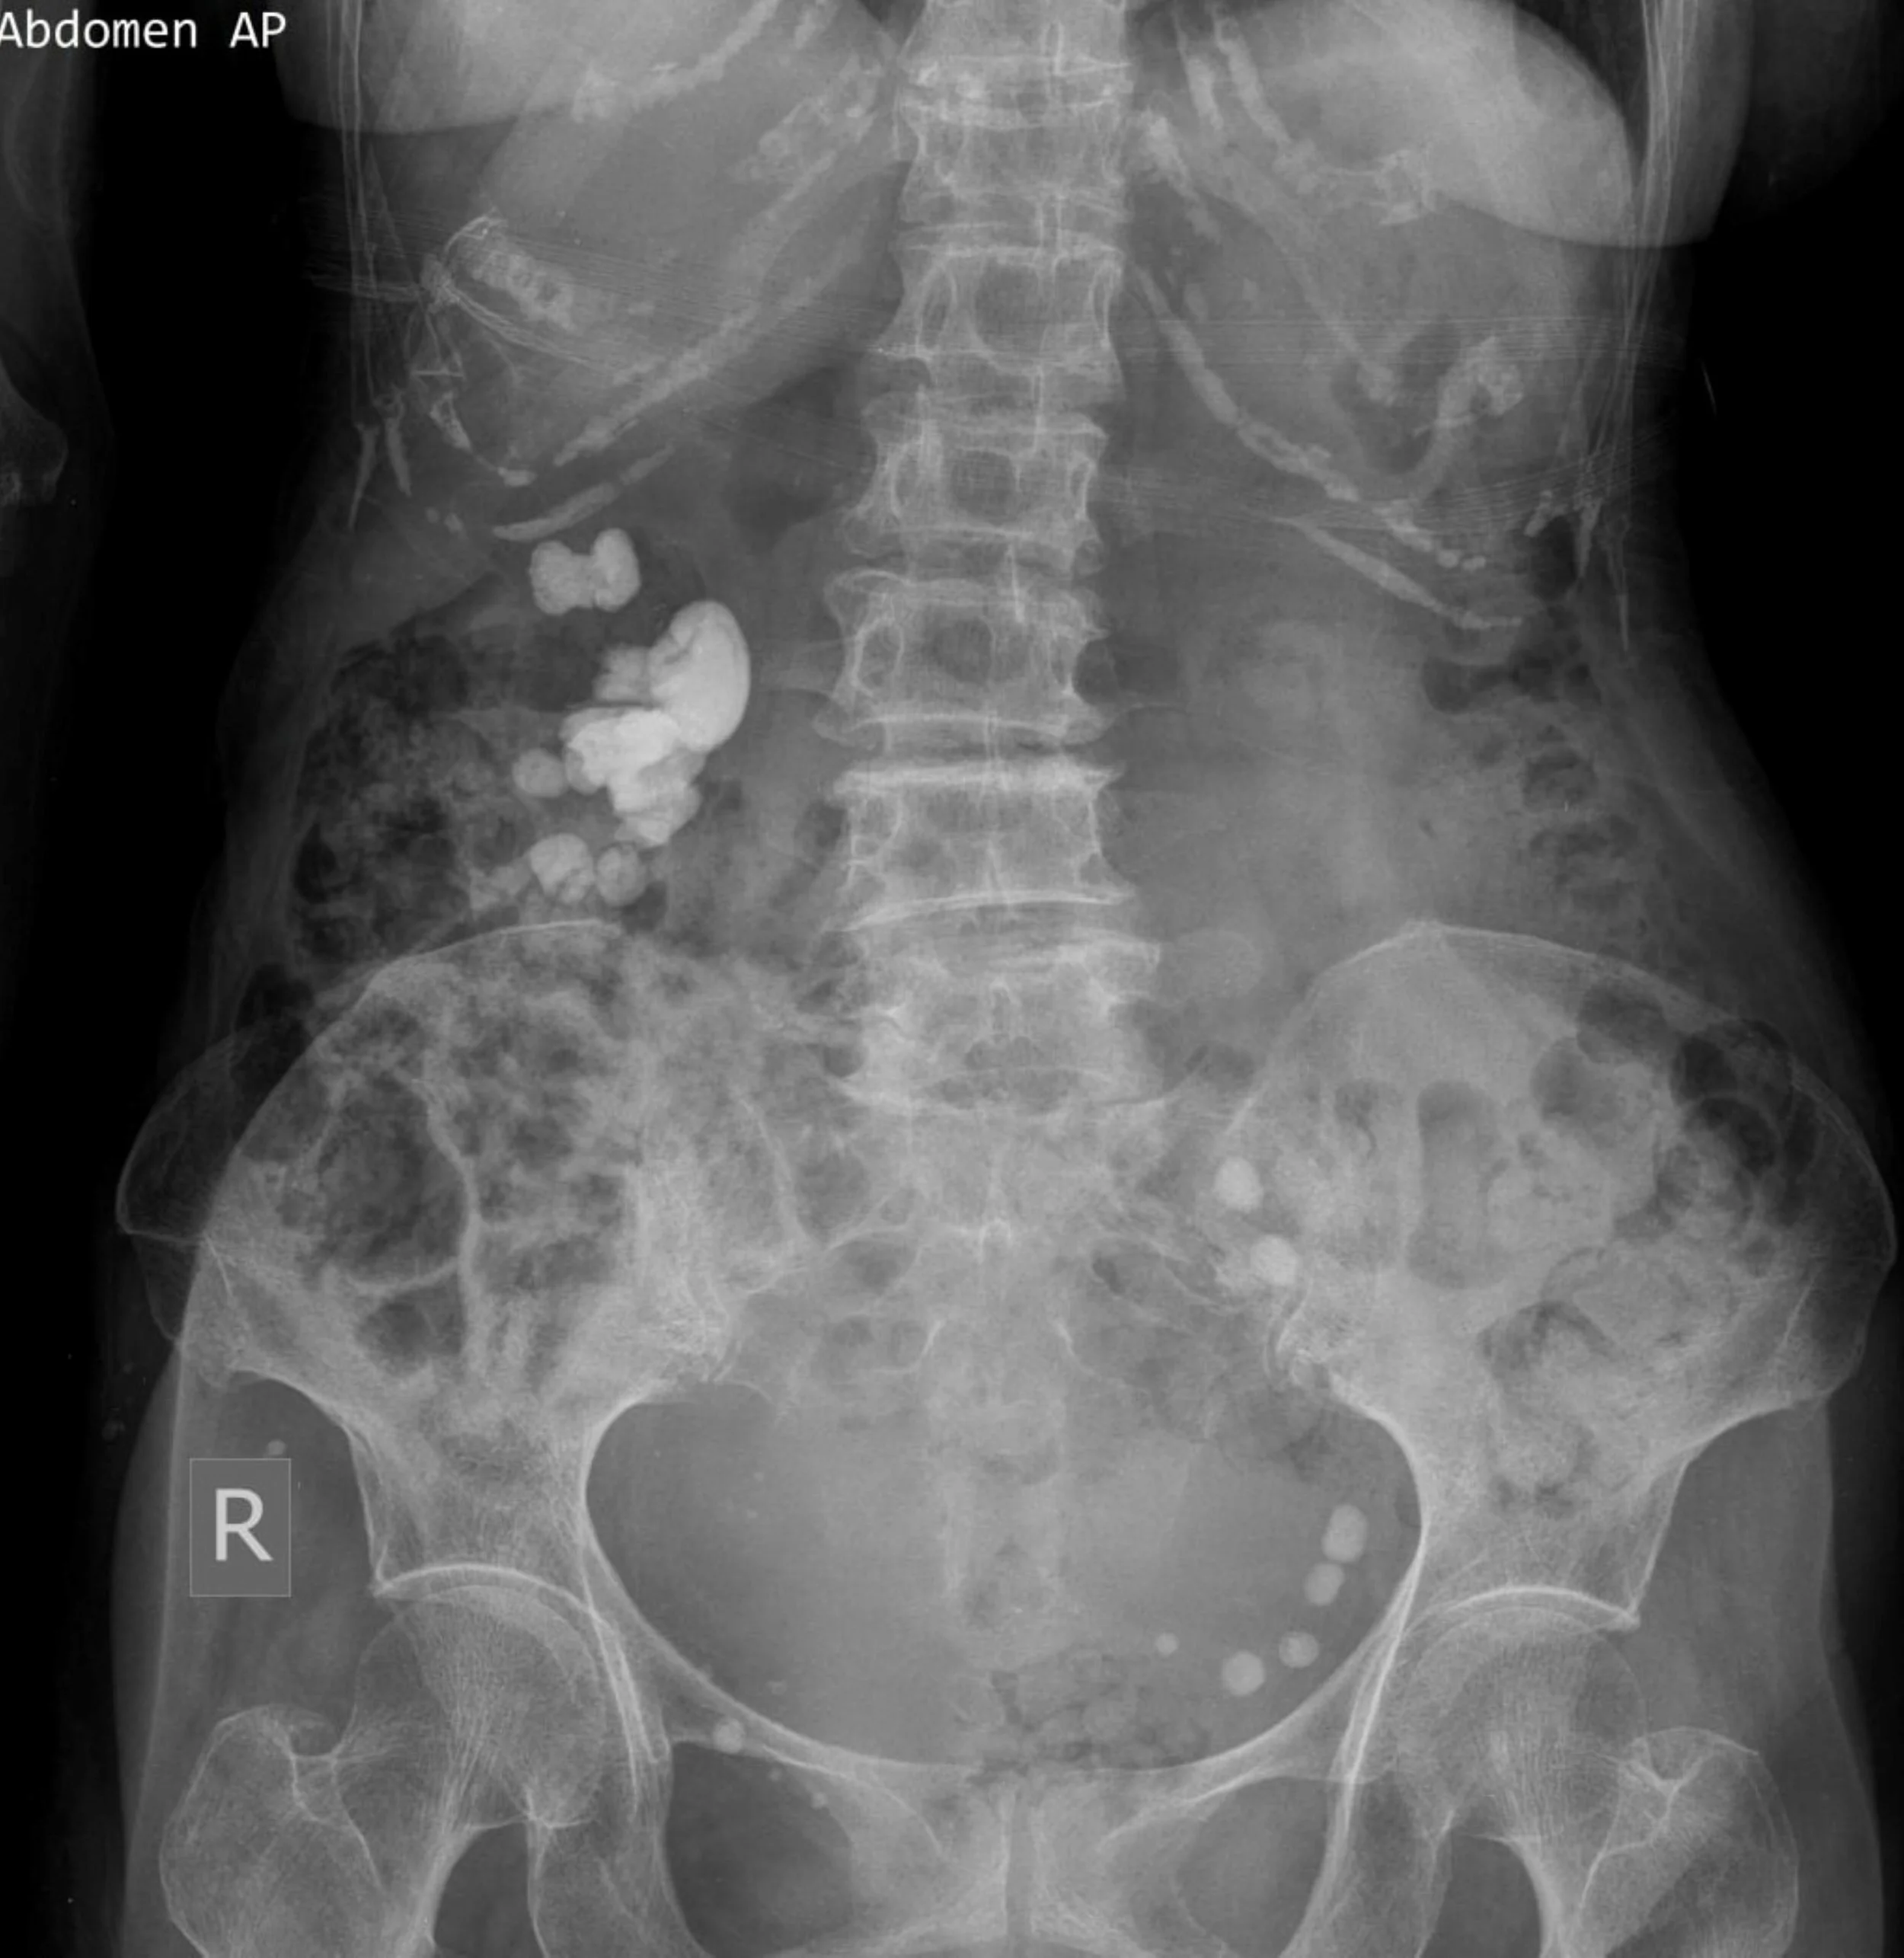

Raio X de abdômen mostrando coluna, pelve, vértebras, cólon e outros órgãos internos.